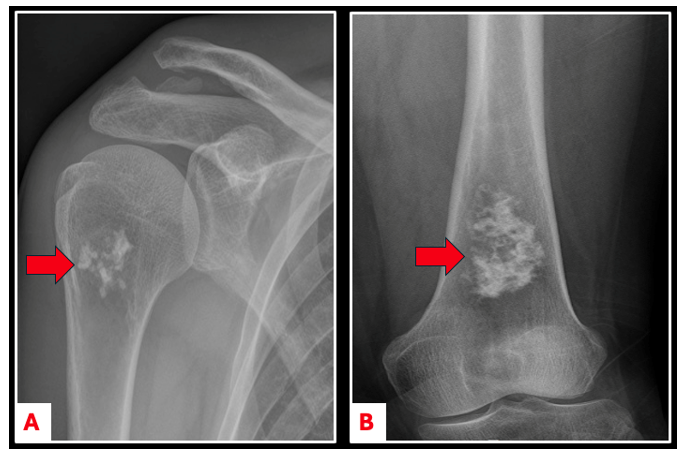

On an X-ray, enchondromas look like an area with white, popcorn-like spots in the middle of the bone (Figure 1). In small bones like the fingers and toes, the bone around the bump may look a little wider or expanded (Figure 2A).

Figure 1. Anterior-posterior (AP) imaging of an enchondroma in the proximal humerus (A) and in the distal femur (B).